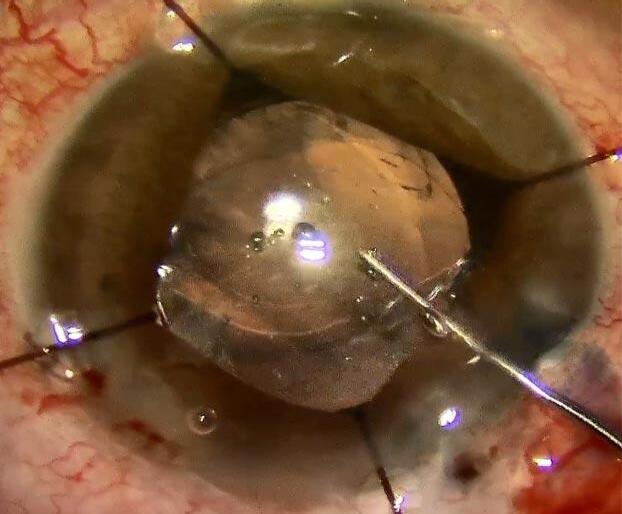

Capsulorrexis posterior tras rotura de la cápsula posterior

Autores: Dr. Agustín Magnetto. Fundación Zambrano - Hospital Lagleyze. y Dr. Tomás Jaeschke. Instituto de la Visión - Hospital Lagleyze.

La rotura de cápsula posterior (RCP) es una de las complicaciones más frecuentes en la cirugía de facoemulsificación con reportes entre 0,5% y 5,2%. La prevalencia de la misma disminuye notablemente si se tienen los reparos necesarios para su preservación, principalmente en la técnica de facoemulsificación y los parámetros utilizados en el equipo. La estabilidad de la cámara anterior en los últimos fragmentos es clave para la seguridad siendo los principales factores el vacío máximo programado en el equipo con el consecuente surge tras la desoclusión de la punta (Imagen 1) , la pérdida incisional de líquido y la tecnología compensatoria que nos pueda ofrecer cada equipo.

Si nuestra intención es colocar una lente, ya sea en el sulcus o en el saco capsular, es vital la estabilidad de la rotura. Si ésta se agranda irregularmente perderemos soporte para la lente y tendremos mayor riesgo de propaso vítreo, tanto por el área de la apertura como por el posible compromiso de la hialoides anterior.

Una de las maniobras que nos ayudan a contener una RCP es la capsulorrexis posterior (Imagen 2)

El concepto principal a destacar a la hora de justificar esta maniobra es lograr la continuidad del borde de la capsulorrexis. Como bien sabemos por tratar con la cápsula anterior en cada cirugía de catarata convencional, la pérdida de la continuidad en la “rexis” es factor fundamental para que tengamos una “fuga”, es decir una extension radial en la apertura de la cápsula. Este concepto aplica de la misma manera a la cápsula posterior. Por lo cual, cuando tenemos una solución de continuidad en la cápsula posterior, cualquier maniobra que realicemos puede aumentar su tamaño. Desde la colocación de viscoelástico, vitrectomía anterior, colocación de la lente, hasta disbalances de presión entre el segmento anterior y segmento posterior.

Existen RCP que son evidentemente irregulares y con bordes discontinuos, pero también nos podemos encontrar con una apertura aparentemente circular (Imagen 3) , sobre todo cuando la rotura sucedió con súbitos colapsos en la cámara anterior y la cápsula entra en contacto brevemente con el tip del faco o de la bomba de aspiración. Incluso en esta situación no nos debemos fiar de la continuidad, ya que puede haber microdesgarros en el borde que extiendan la apertura en las maniobras subsiguientes.

Si diagnosticamos la RCP a tiempo y logramos realizar las maniobras para evitar el prolapso vítreo, podemos proceder a realizar la capsulorrexis.

El primer paso es colocar viscoelástico a la altura de la rotura para alejar la hialoides anterior, que en el mejor de los casos estará intacta, y el viscoelástico se ubicará uniformemente en el espacio de Berger. (imagen 4)

Una vez que tenemos compartimentalizado el segmento anterior procedemos a tomar un cistitomo o una microtijera y generar un corte sobre uno de los bordes de la apertura. (Imagen 5)

Luego, con una pinza de capsulorrexis curva o una micropinza tomaremos el flap y comenzaremos con las maniobras. Debemos tener en cuenta que la cápsula posterior es elástica, similar a la cápsula anterior de pacientes jovenes, por lo cual debemos realizar una maniobra de ripping con direccionamiento centrípeto. ( imagen 6)

Una vez que generamos una apertura circular y continua, colocaremos viscoelástico nuevamente y procederemos a realizar vitrectomía anterior de ser necesario. En este caso con menor posibilidad de extension del desgarro por la estabilidad que nos brinda la regularidad de la apertura.

Una capsulorrexis posterior continua nos habilita a colocar una lente en el saco capsular. La cual podremos colocarla en el sulcus y luego luxarla al saco capsular, o inyectar la primera háptica directamente en el saco para luego colocar la segunda háptica con maniobras rotatorias, siendo esta una maniobra más arriesgada. Corregir la continuidad de una RCP nos permite incluso colocar una lente tórica monopieza en el saco en caso que tengamos esta complicación. (Imagen 7)

En caso de que la apertura tenga un mayor tamaño y exista la posibilidad de colocar una lente de tres piezas, podemos colocar la misma en el sulcus. En este caso, una maniobra adecuada para lograr mayor estabilidad del implante, predictibilidad refractiva y una mayor compartimentalización entre segmento anterior y segmento posterior es la captura óptica. (Imagen 8)

En conclusión, en caso de tener una RCP, estabilizar la rotura con una capsulorrexis circular continua posterior nos dará mayor seguridad a la hora de realizar los pasos subsiguientes y nos permitirá colocar una lente en el saco capsular, especialmente en caso de que el implante planeado sea monopieza.